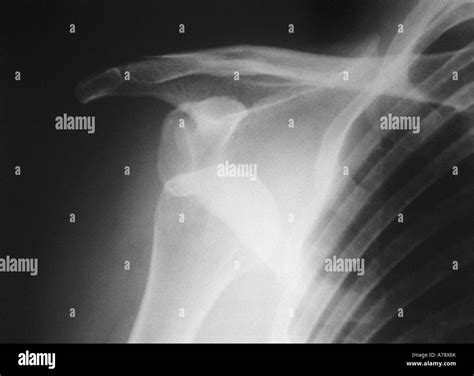

Experiencing a sudden, sharp pain in your shoulder after a fall or a sports-related impact is a distressing ordeal. Often, the first thing medical professionals will order to assess the situation is a Dislocated Shoulder X Ray. Understanding why this imaging is critical, what it reveals, and how it guides your recovery journey is essential for anyone dealing with this common orthopedic injury. A dislocated shoulder occurs when the ball of your upper arm bone (the humerus) pops out of the shoulder socket (the glenoid). Because this area is complex, precise imaging is the gold standard for confirming the diagnosis and ruling out associated complications.

• Visualizing the position of the bones: It confirms whether the humerus is truly out of the socket or if there is a partial dislocation (subluxation).

• Assessing alignment: It helps doctors identify the specific type of dislocation—whether it is anterior (forward), posterior (backward), or inferior (downward).

• Anteroposterior (AP) View: Taken from the front, this view helps doctors see the general relationship between the humerus and the socket.